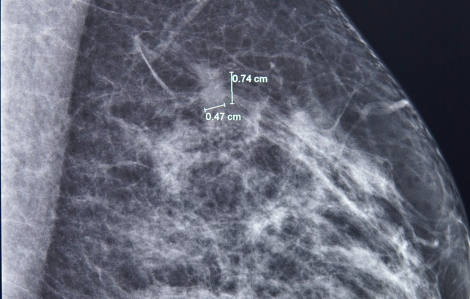

Ung thư vú đa ổ kích thước rất nhỏ (7mm và 3mm) được phát hiện trong lần tầm soát vú định kỳ.

Điều đáng sợ nhất không phải là phát hiện ra ung thư vú - mà là phát hiện ung thư vú ở giai đoạn muộn.